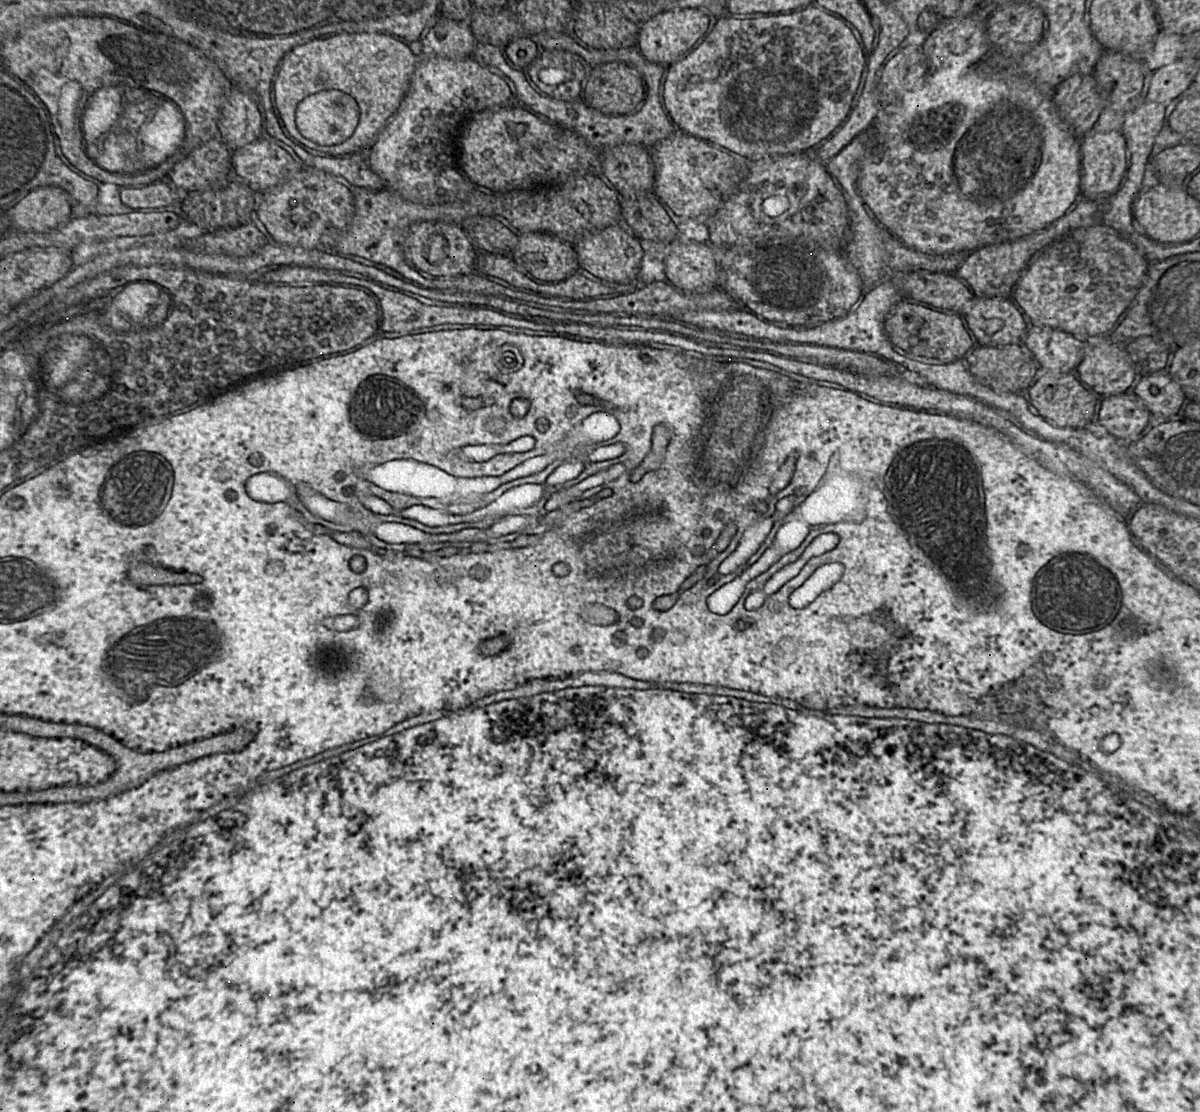

Detalle del proceso de sinapsis, por el que se transmite el impulso nervioso.

Entre los usos más frecuentes del microscopio electrónico de transmisión que posee la Universidad en el edificio multiusos I+D+i de la calle Espejo están el análisis de las características de la cristalización y la estructura microscópica de materiales. En cuanto a las muestras biológicas, permite muchas y variadas posibilidades como analizar alteraciones celulares en patologías y la organización subcelular de organismos, plantas, bacterias y virus.